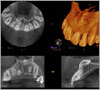

最近では3D関連の技術が進歩しています。そのため手術を事前にコンピューター画面上でシミュレーションするソフトが当院にはあります。

更に当院では骨量が少ない難症例の場合には患者さんのCT情報から3Dプリンタを使用して3D顎顔面の骨の実寸大の模型を作り治療に役立てています。

当院では院内に歯科用CTを完備しております。安全にインプラント手術を行うには、術前はもちろんのこと、術中・術後にもCT撮影が不可欠になります。医科用CTは断面スライス幅が0.5mm~1.0mmに対し、歯科用CTでは0.075mmまで設定できるので、精密な診断が可能になりました。

術前・術中のCT撮影により、従来のレントゲン撮影では分からなかった骨の厚みや神経・血管の位置が、歯肉を切開しなくても診断可能になりました。当院ではインプラントの90%はフラップレス手術です。ほぼ無痛・無出血、手術時間もたったの15分で患者様に優しい最新の治療法です。フラップレス手術を行っているクリニックは現在5%未満です。インプラント専門医ならではの治療法。

インプラント治療を適切に行うためには、顎の骨の状態を詳しく調べることが重要です。

そこで、治療前にCT撮影を行い、最先端の3Dシミュレーションを使用し、顎の骨の状態を見ながら治療計画を立てます。これが、より安全で無理のない治療を進めるための最新の方法です。